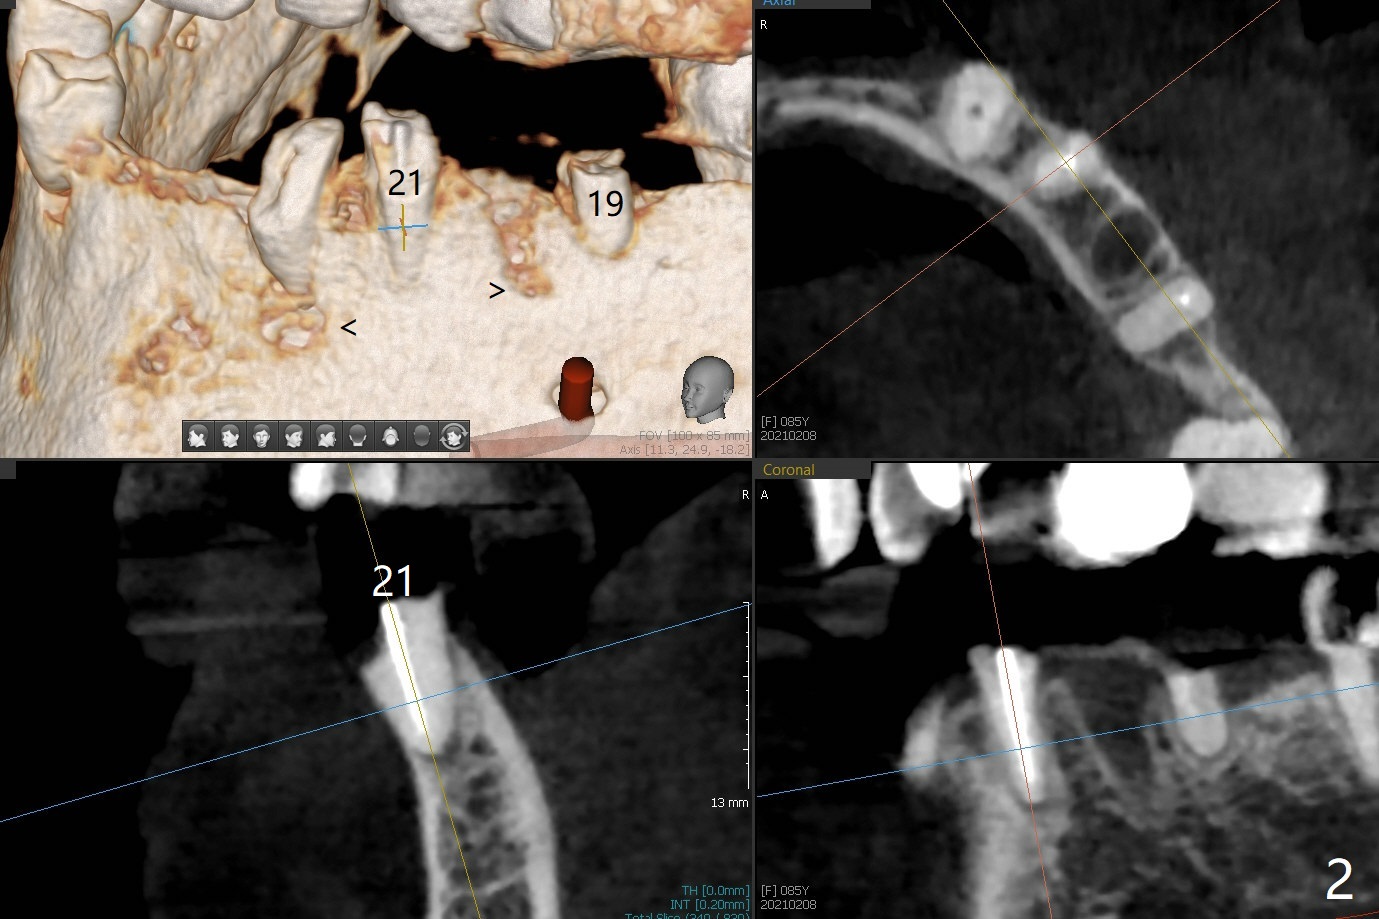

85岁女回诊所做27,28,30植牙,由于导板设计,所有7个残根需要拔除(图一,三),做过根管治疗牙齿(图一:箭头),如19,21号牙,颊侧骨板吸收比没做过的轻(图二,四:箭头(根尖穿孔))。30号牙根尖吸收多,使用短小植体(图五),根尖骨质少,初步稳定性差,不能即刻修复(图六),是这次手术最大欠缺的部分。原来准备在30号牙位做临时牙冠,局部托牙卡环恢复作用,还好27,28植体(图八)稳定性好,连体临时牙冠帮助托牙固定。27,28植体不足之处是放置太深,基台与牙槽骨(图八:*)接触,可能造成骨质吸收。其实27号植体(3.5x9mm)植入后必须去除,与基台连接后,一起徒手植入,所以深度控制不好。术后一个月10天病人回来做20和22号牙种植(拔牙后一,两个月),由于角化龈窄,切开导板植入,好处容易判断22号牙植体深度,植深后,两个植体周围放置骨粉(图九,十),然后胎盘膜(两个8x8毫米),4-0 PGA缝线。